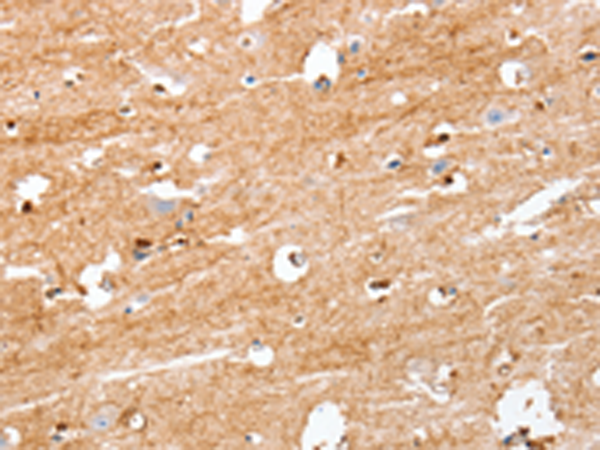

IHC positive control: |

Human brain |

IHC Recommend dilution: |

25-100 |